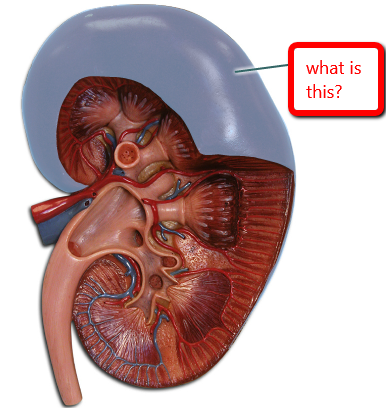

Renal capsule

Renal cortex

Renal medulla

Medullary pyramids

Renal columns

Renal Pelvis

Calyx (of the kidney)